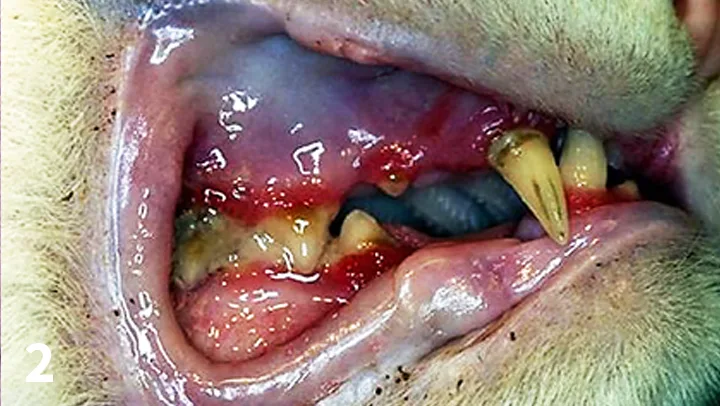

Gingivostomatitis–chronic active inflammation of the mucosa and submucosa–presents with erythematous, ulcerative and/or proliferative lesions commonly found on the gingiva, buccal mucosa, lips, palatal glossal folds, lateral pharyngeal walls, and lateral aspects of the tongue.2-4 (See Figure 1.) No sex, age, or breed predilection exists. The median age of patients with this disease is 7 years.2

Gingivostomatitis showing the extent of oral inflammation. All photos courtesy of the author unless noted otherwise.